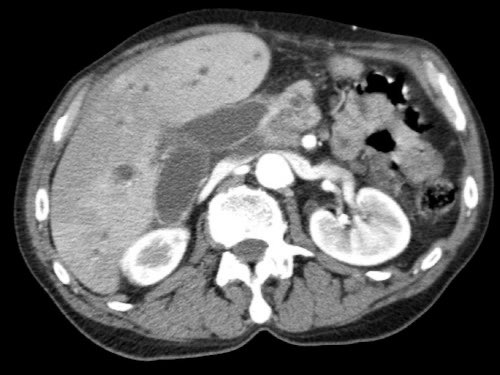

CT axial cho thấy:

- Khối u ở thân tụy (đầu mũi tên trắng).

- Tiếp xúc khu trú < 90º với động mạch mạc treo tràng trên (SMA).

- Tiếp xúc rộng hơn từ 90º – 180º với SMV, SMV bị hẹp nhẹ và biến dạng (mũi tên vàng).

- Giãn ống tụy